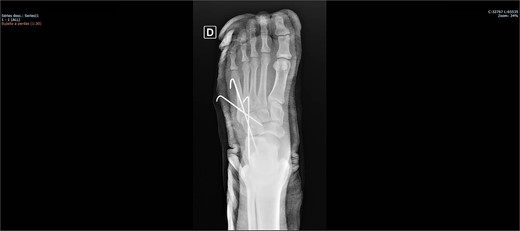

The patient was placed on the surgical table in the supine position, anesthetized with spinal anesthesia, and given prophylactic antibiotic therapy with 2 g of cefazolin. After exsanguination of the lower limb, a dorsolateral incision was made on the foot over the cuboid bone and deepened through the layers until complete visualization of the cuboid bone was achieved. There was an interposition of ligamentous structures, such as the calcaneocuboid ligament, dorsal cuneocuboid ligament, and dorsal tarsometatarsal ligaments. After removing all structures that were interposed and preventing reduction, the cuboid was reduced easily, but instability was observed. Due to the instability found, percutaneous fixation was performed with three Kirschner wires: the first extending from the fourth metatarsal to the calcaneus, traversing the cuboid; the second from the fifth metatarsal to the cuboid; and the third from the cuboid to the calcaneus, from anterior-dorsal to posterior-plantar (Figs 3 and 4). After complete fixation, the stability of the cuboid was observed, maintaining it in the correct position, confirmed with fluoroscopy during surgery.